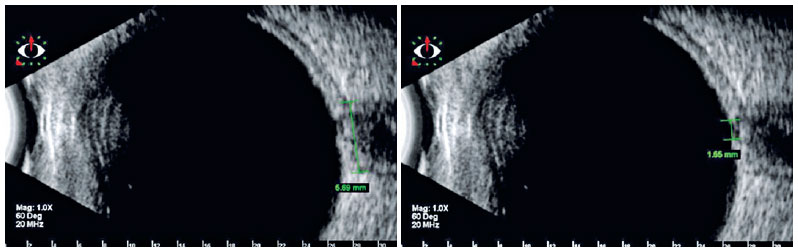

Ultrasonography

Ultrasonography has been widely used in investigations related to the diameter and, contiguously, sheath of the retrobulbar optic nerve in glaucomatous optic neuropathy(41-43). Reduced sectional dimensions in patients with glaucoma as compared with healthy individuals were attributed to the loss of nerve fibers that occurs in this disease. It is a noninvasive and easily accessible method, which can be used to investigate the disease, especially in cases where the morphology of the optic disc does not allow a conclusive diagnosis or in the presence of opaque media, which makes visualization of the optic nerve head difficult or even impossible(42,43). Figure 3 illustrates an example of an optic nerve head observed on ultrasonography.